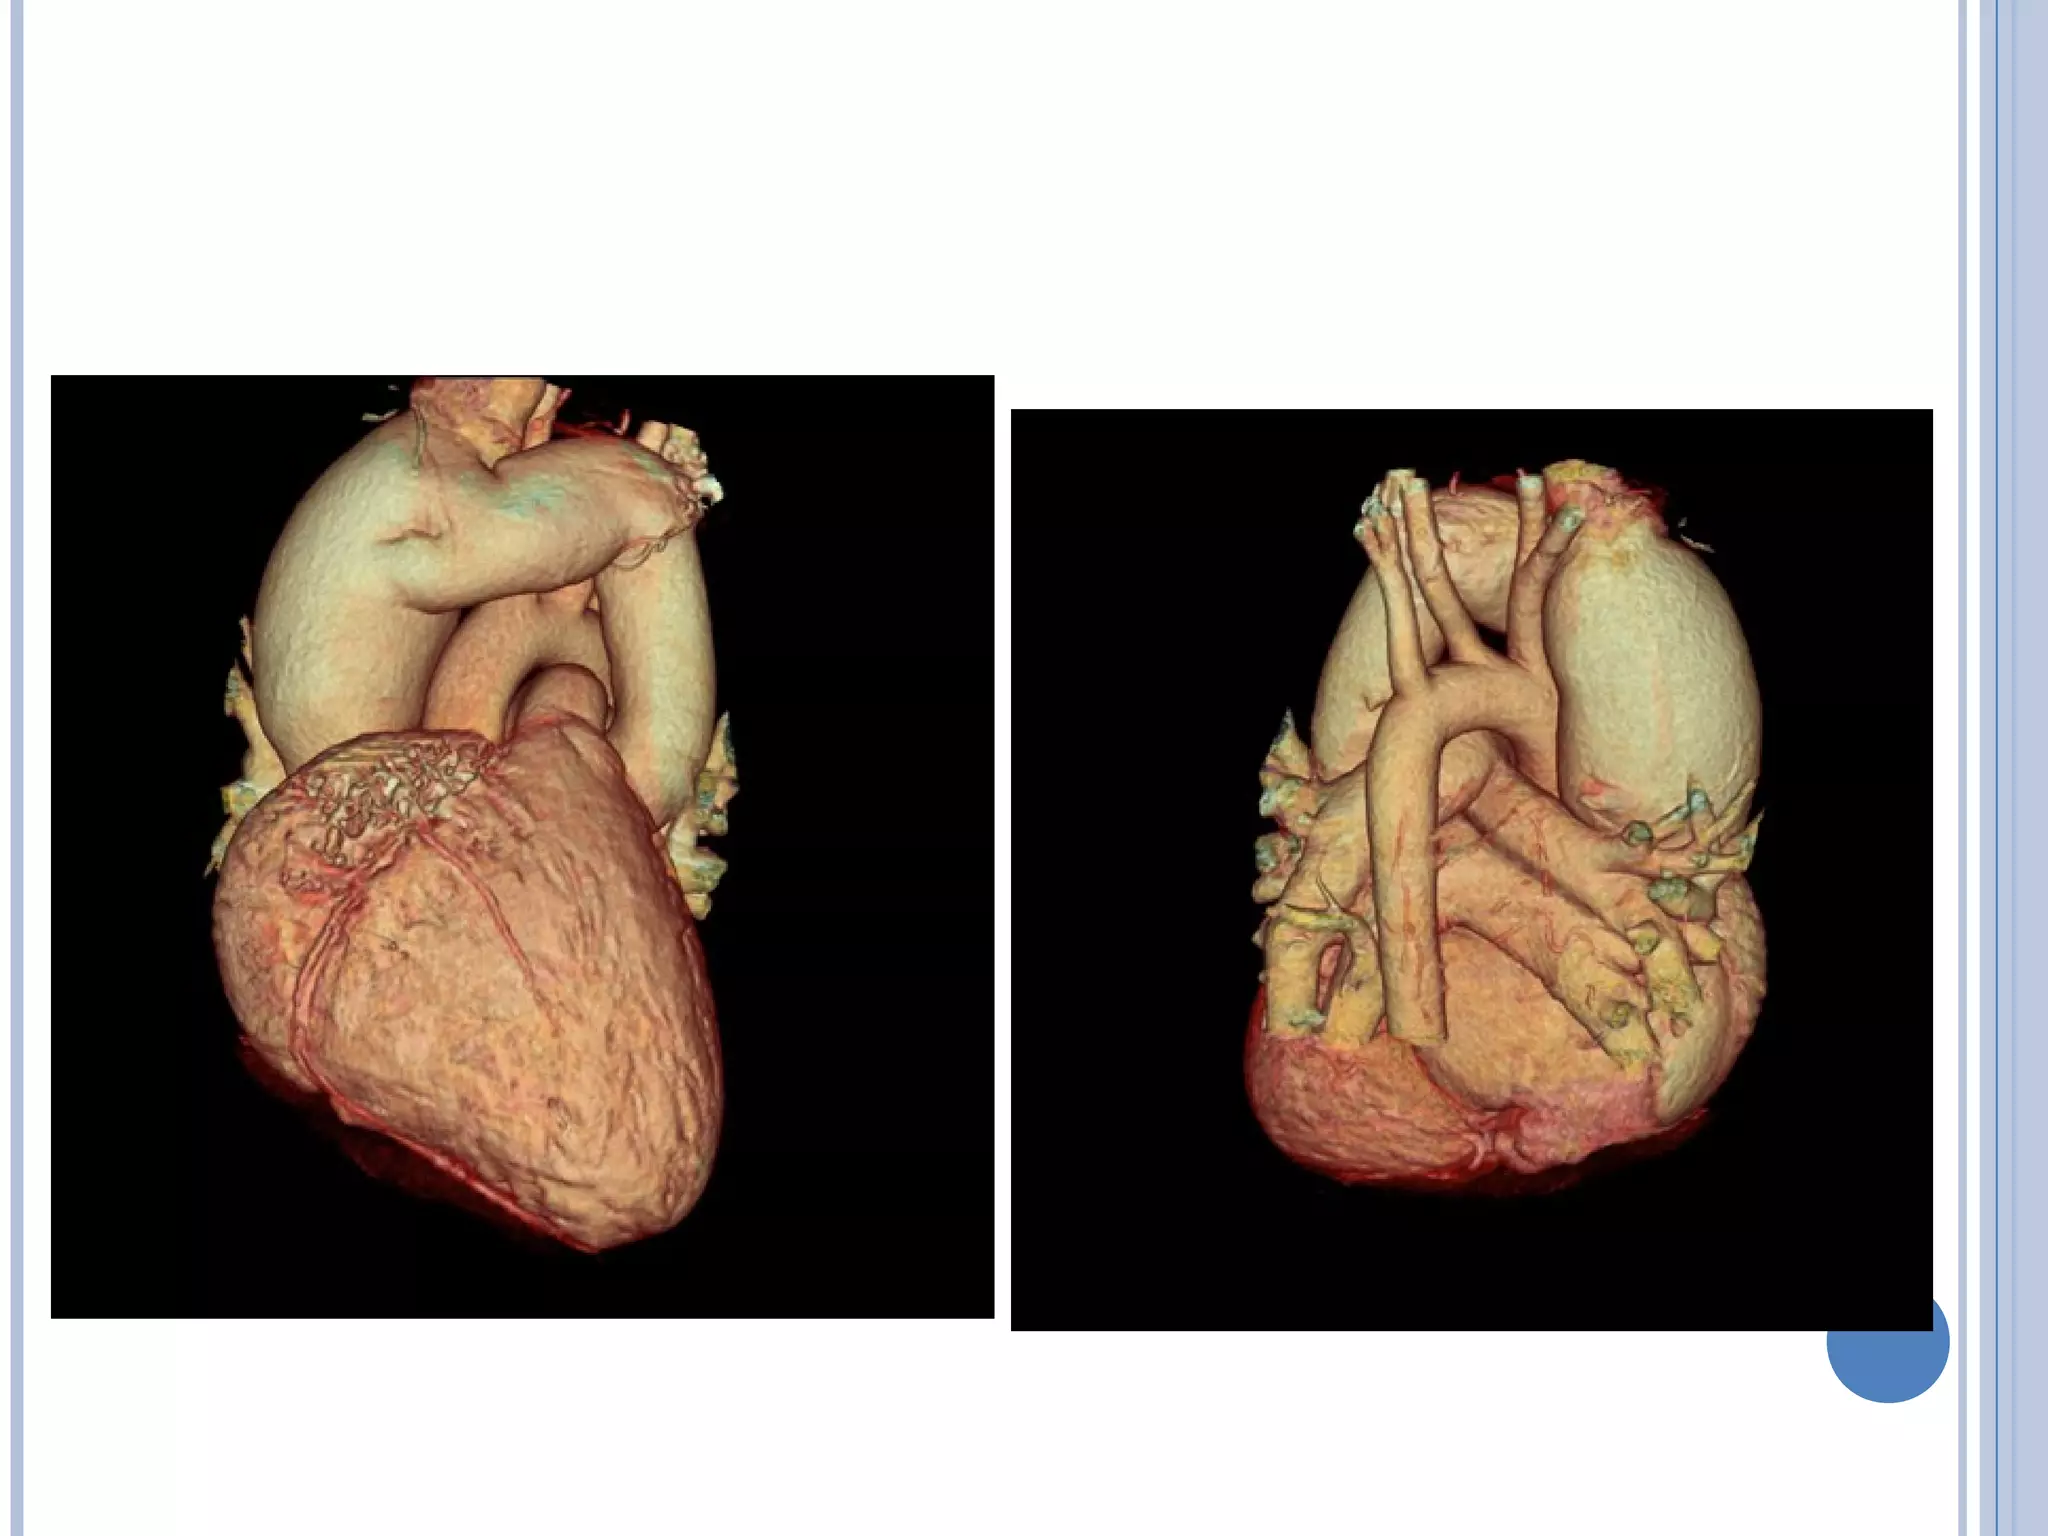

• #25 TAPVR: Anatomy- Supracardiac 1 Gross anatomy of supracardiac total anomalous pulmonary venous return. Pulmonary veins (PV) drain to a vertical vein that connects to the right atrium (RA) via the innominate vein and superior vena cava (SVC). Other abbreviation: RV right ventricle  TAPVC: Anatomy- Coronary Sinus Posterior view of gross anatomy of total anomalous pulmonary venous return to the coronary sinus. The coronary sinus has been opened longitudinally. The right forceps is grasping one side of the coronary sinus wall. The left forceps is grasping the left atrial appendage (LAA). The left (LPV) and right (RPV) pulmonary veins enter the coronary sinus. Through the opened coronary sinus, a patch can be seen that covers the coronary sinus os in the right atrium. TAPVR: Anatomy- Infradiaphragmatic 2 Posterior view of gross anatomy of infradiaphragmatic total anomalous pulmonary venous return. The right (RPV) and left (LPV) pulmonary veins enter a vertical vein that courses through the esophageal hiatus to connect to the portal venous system.